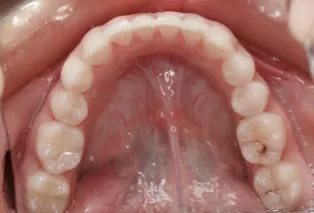

Intraoral photos